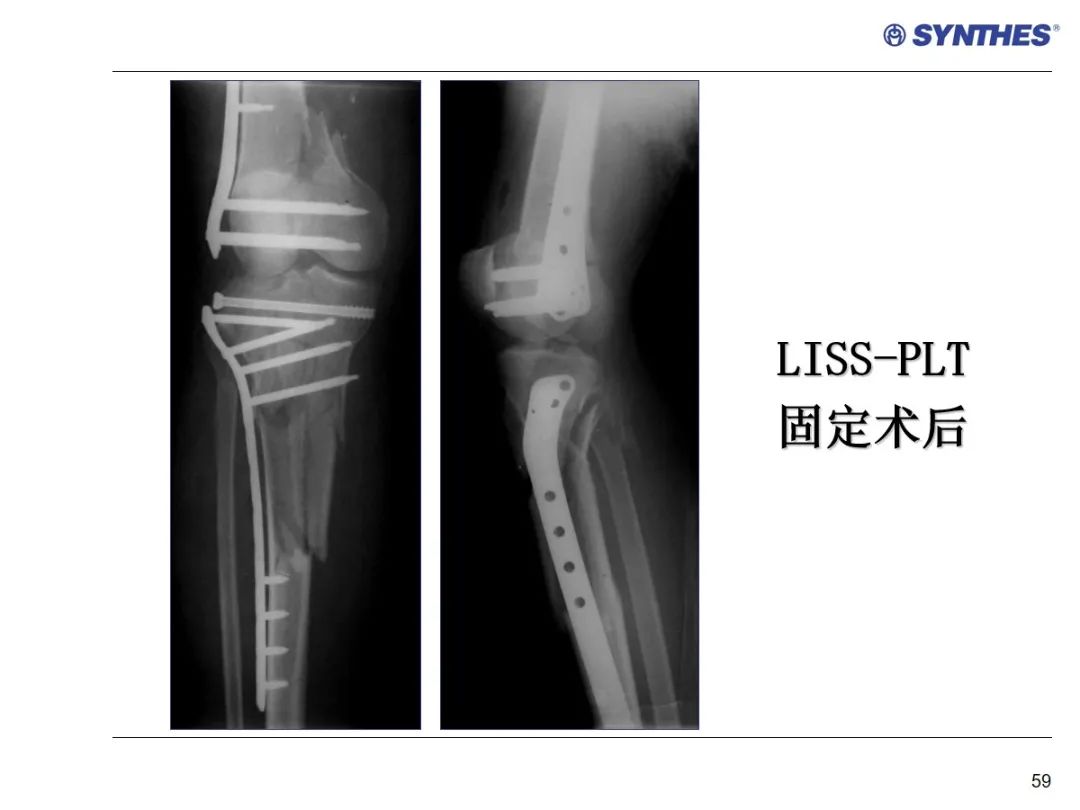

LISS微创固定系统应用技巧,原来如此简单!